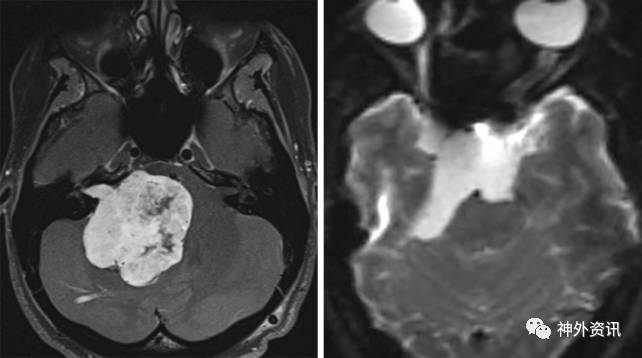

图1. 巨大的前庭神经鞘瘤(左)和脑干腹侧的表皮样囊肿(右)皆可通过扩大乙状窦后入路切除。

与各种岩骨切除术比较,并发症更低的扩大乙状窦后入路在暴露脑干腹外侧及腹侧病变时同样具有许多相似的优点,这样看来,前者似乎被过度使用了。肿瘤的位置及大小对选择合适的手术入路起决定性作用,但是当我们犹豫是否需要更大的入路时,肿瘤的质地具有非常重要的参考意义。例如,乙状窦后入路可以切除跨越脑干腹侧的巨大表皮样囊肿,然而包裹血管的脑干腹外侧的质韧脑膜瘤却需要选择岩骨切除术。